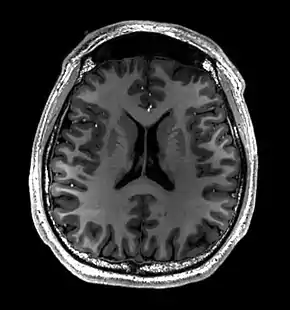

MRI of Brain

Cross-sectional T1-weighted MRI of a healthy human brain acquired with an ultra high-field MR of 7 Tesla field strength

Magnetic resonance imaging of the brain uses magnetic resonance imaging (MRI) to produce high quality two-dimensional or three-dimensional images of the brain and brainstem as well as the cerebellum without the use of ionizing radiation (X-rays) or radioactive tracers.